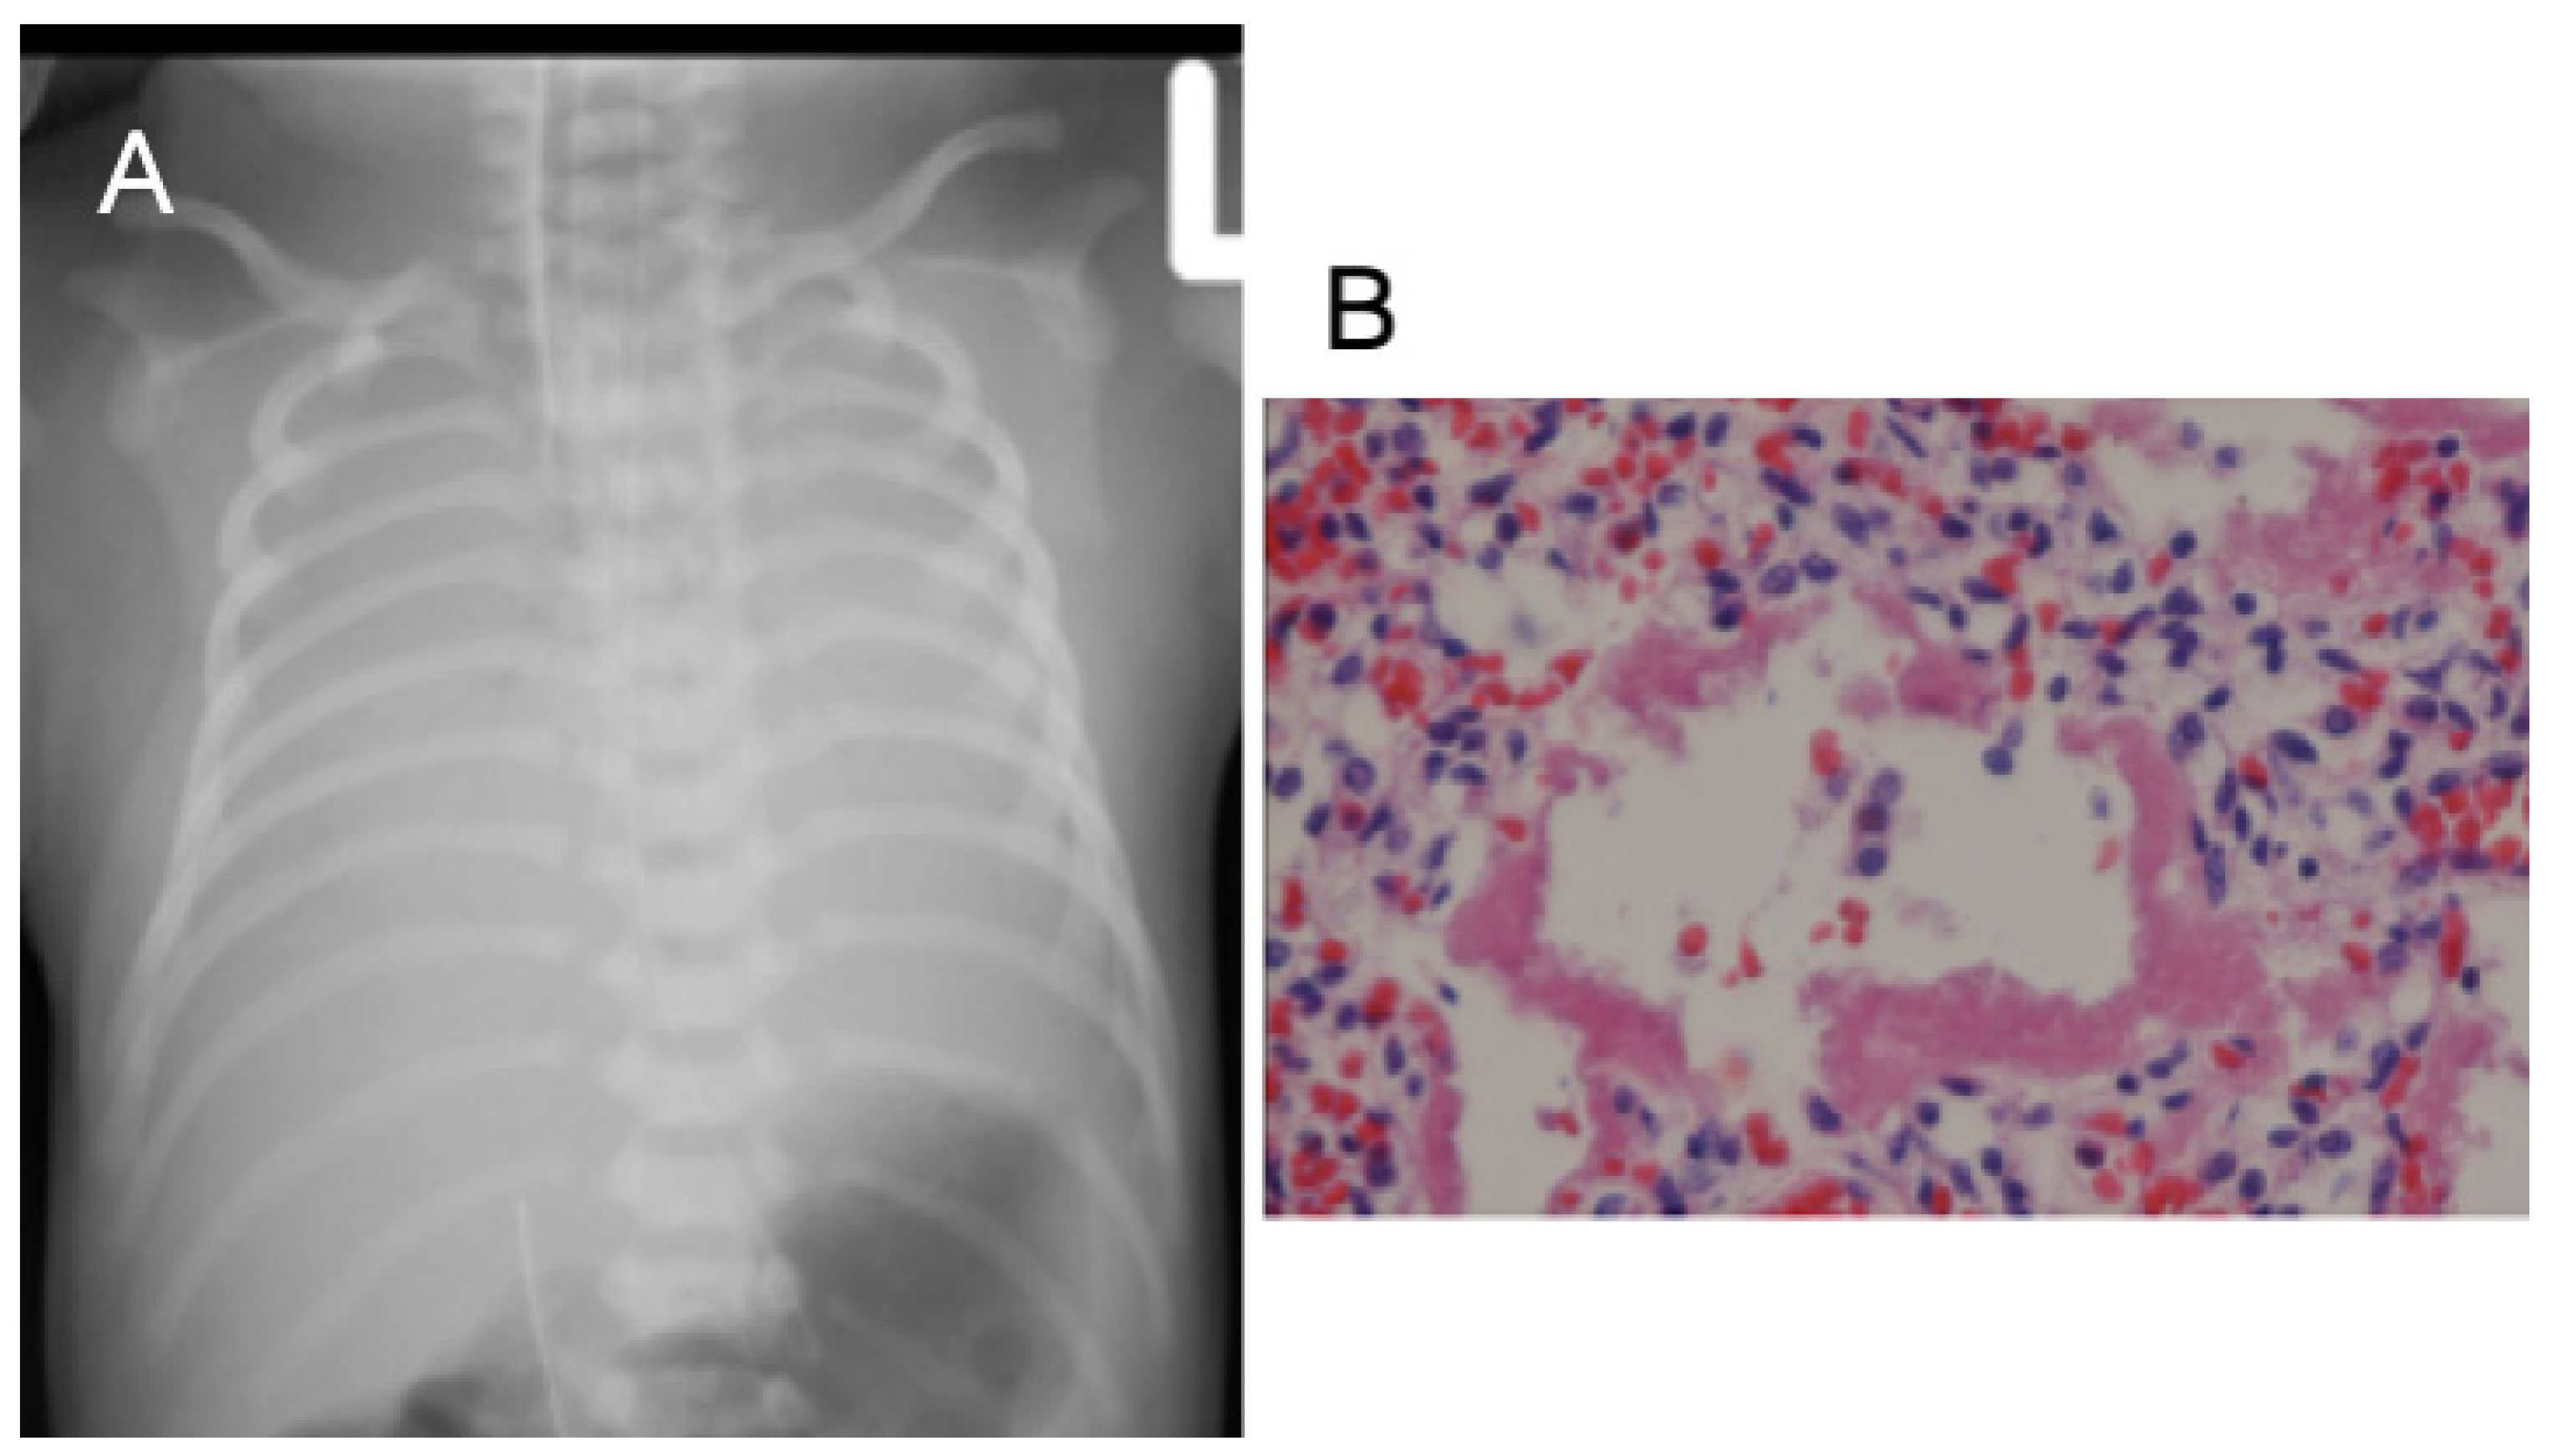

3.1. Case 1

3.2. Case 2